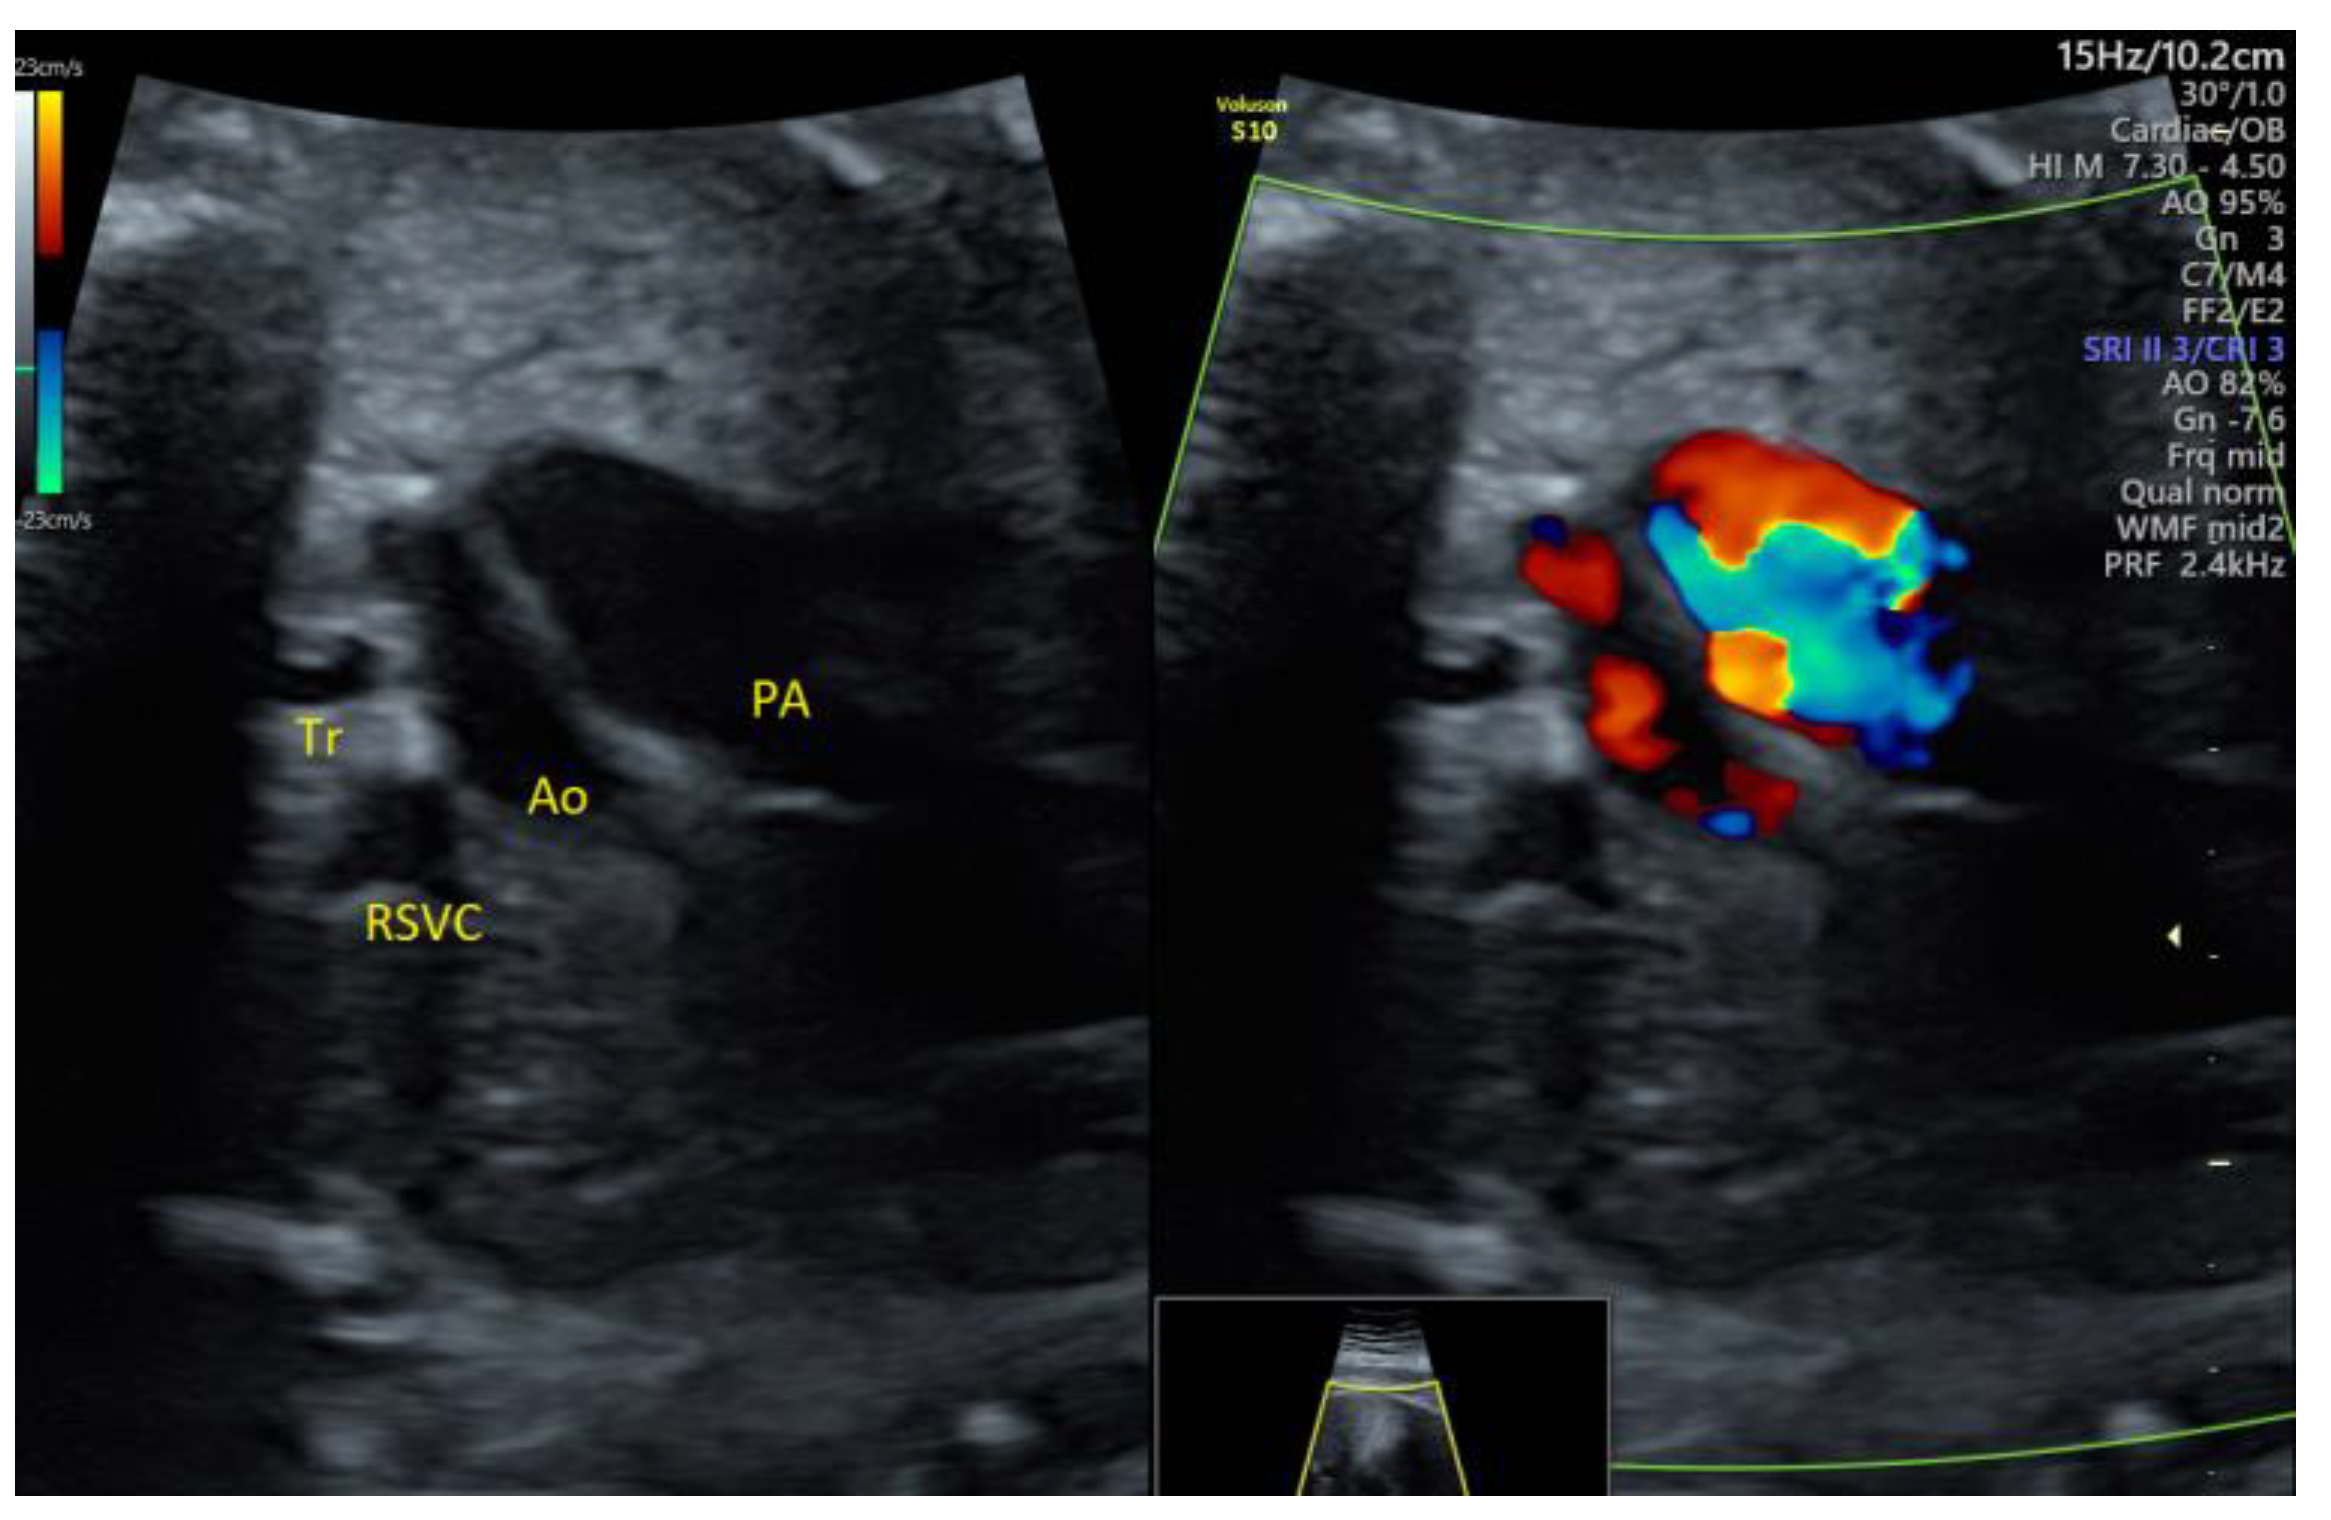

| Valvular PS, mild | 1 | - | - | 3VT | + | 0 | 1 | 0 | 1/1 |

| PA/IVS | 1 | - | - | 4C | + | 0 | 0 | 1 | 1/1 |

| Fallot | 1 | - | - | 3VT | + | 0 | 1 | 0 | 1/1 |

| PLSVC | 4 | - | - | 3VT color | + | 0 | 4 | 0 | 4/4 |